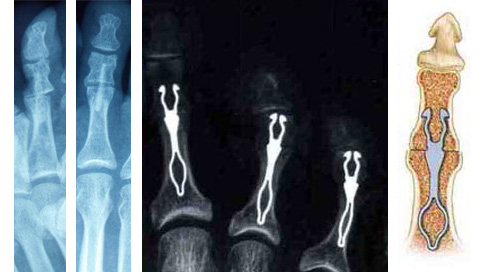

2 - Dans certains cas le blocage de l’articulation inter-phalangienne peut être nécessaire (arthrodèse). La fixation peut se faire sans matériel ; ou dans certains cas une broche sera mise dans l’orteil, et celle-ci sera retirée en consultation 3 à 5 semaines plus tard.